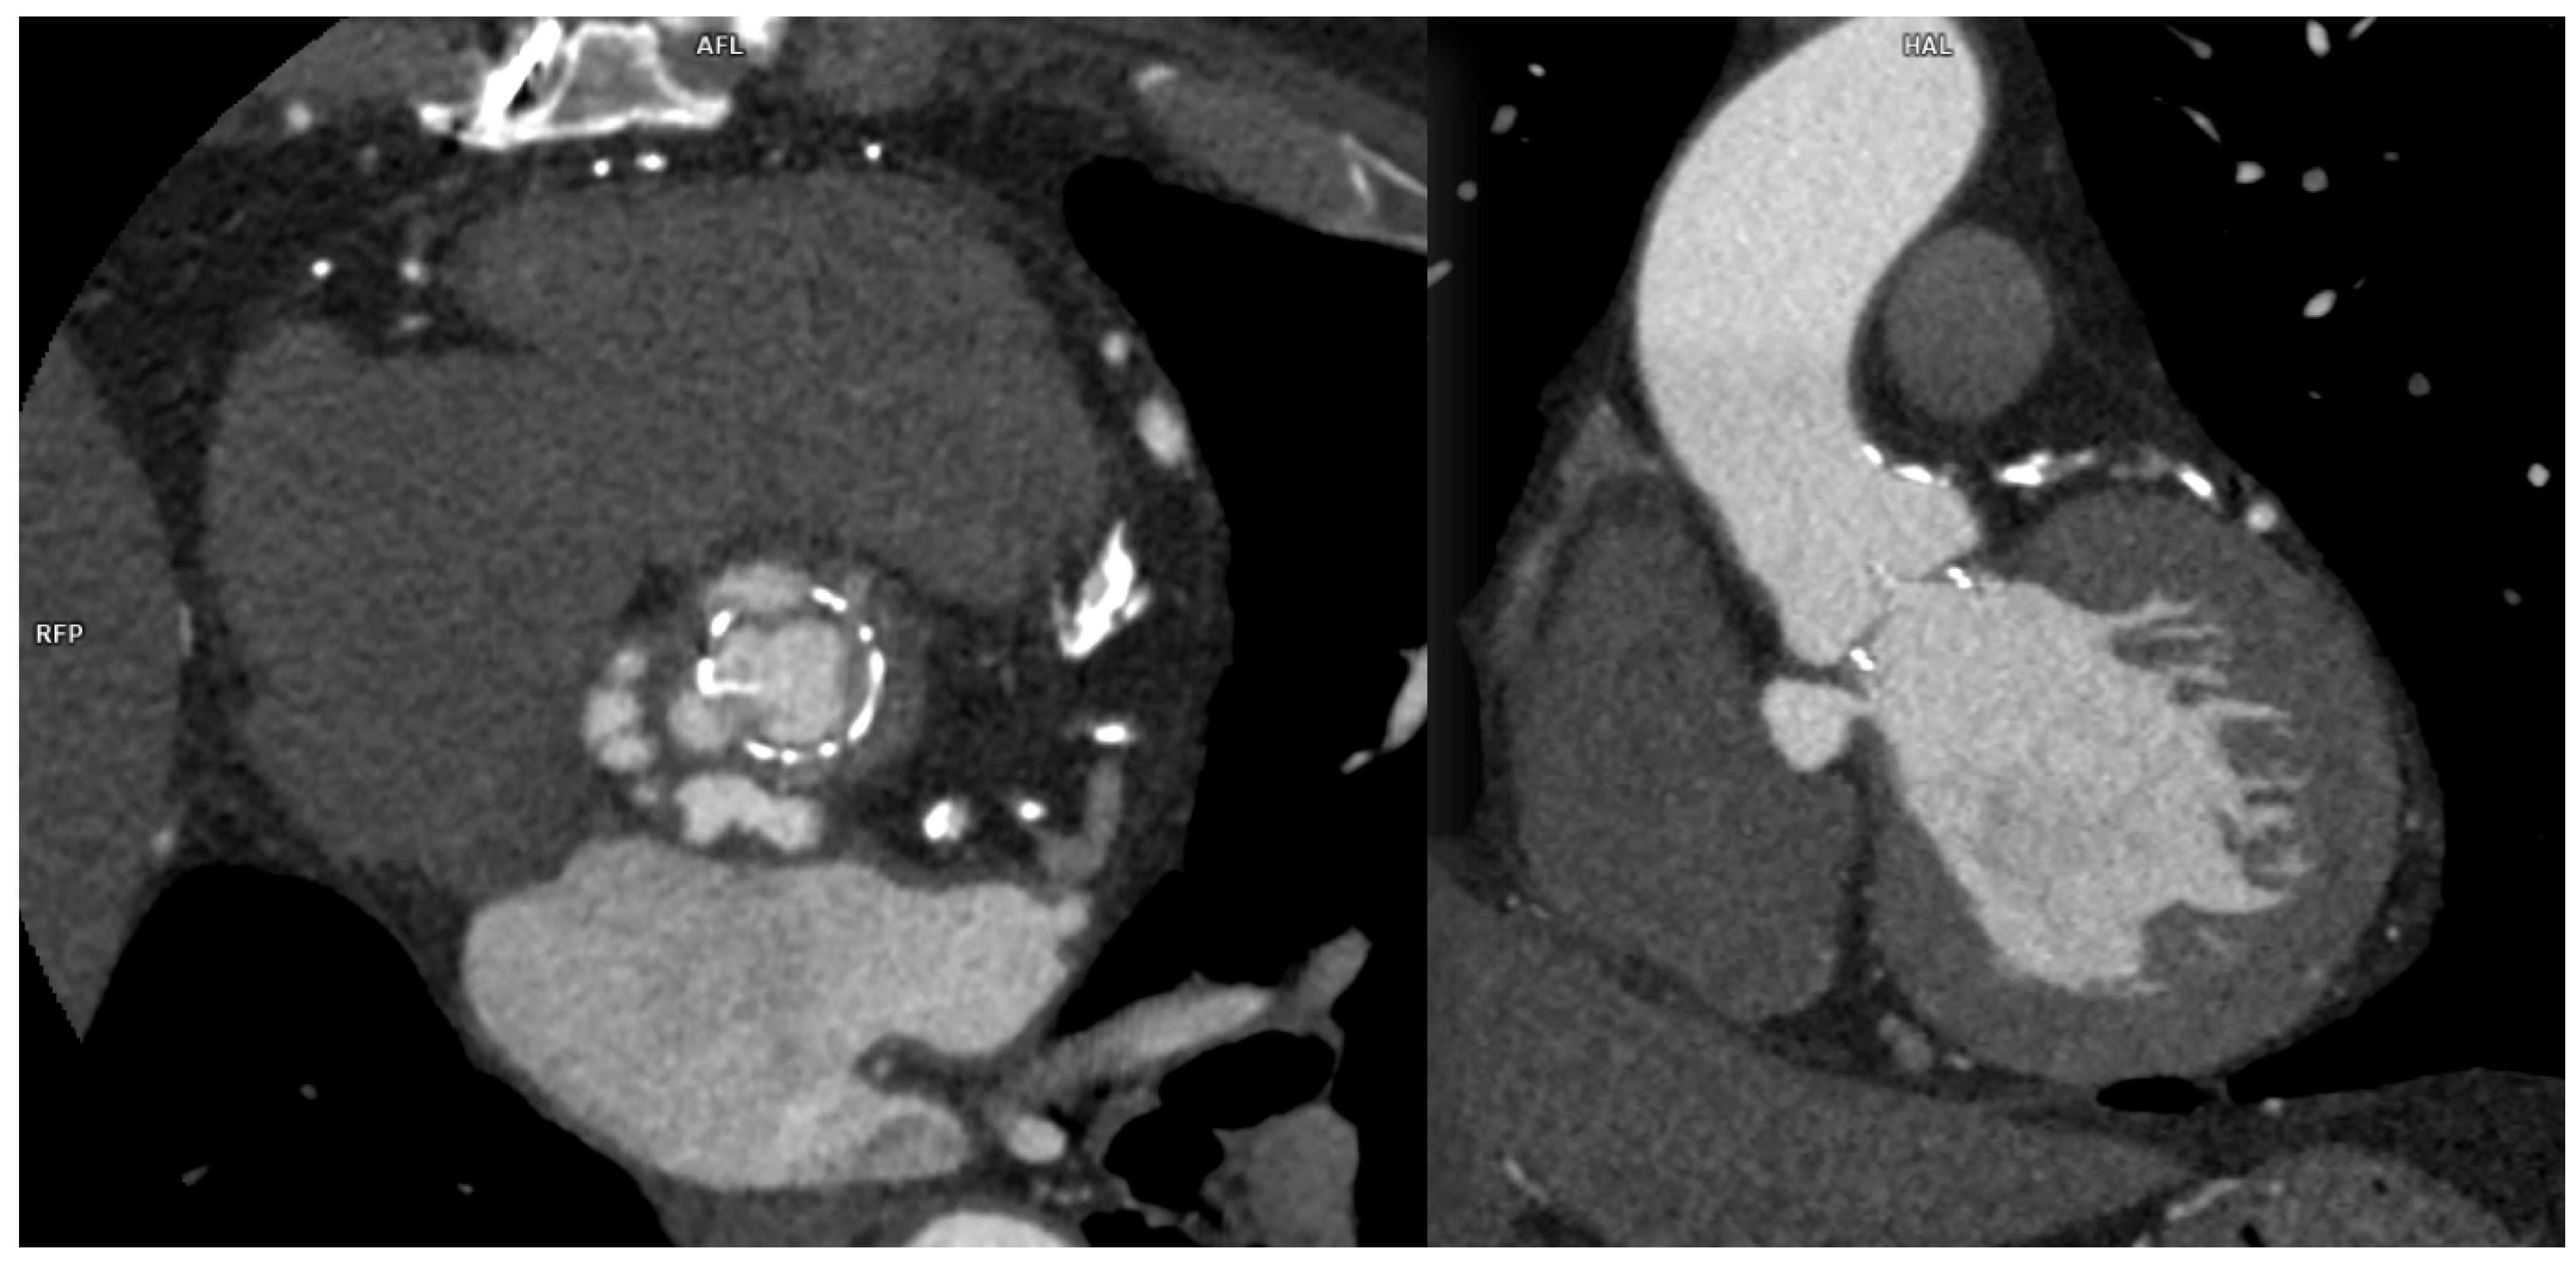

In case of PMK implantation, right atrium or ventricular perforation with associated hemopericardium (Figure 5) was the most common complication (5/27 patients, 18.5%). All pacemakers included in the study had two or three intravenous leads. Cases of damage caused by PMK leads were diagnosed mostly in a chronic phase: 4 by 5 patients, more than 30 days after implementation. Only one case presented as an acute complication (<24 h after PMK placement), showing a more worrying and significant clinical picture, sustained by active bleeding in the pericardial sac.

Pacemaker implantation has become a widely used practice all over the world in a growing population of patients, but thanks to increased indications, complications may be related to pacemaker syndromes that represent the clinical manifestation of a suboptimal synchronization or a mechanical complication related to pacemaker positioning. Complications may be acute or subacute in the setting of pacemaker implantation; the more frequent among them are pneumothorax, cardiac perforation, pocket hematoma or bleeding, lead dislodgement, venous thrombosis, and mechanical lead complications. One of the most insidious inconveniences is represented by perforation of the myocardial wall, both in the acute and subacute phases. Symptoms of perforation include pleuritic chest pain from pericarditis, diaphragmatic or intercostal muscle stimulation, and, in the presence of pericardial effusion, patients may develop shortness of breath and hypotension as the tamponade develops [23].

Complications encountered after PMK implantation represented 18.5% of all cases in the study. One patient only (0.03%) was scanned in the acute phase, less than 24 h after PMK positioning, presenting with acute chest pain, dyspnea, and laboratory signs of anemization. CTA was fundamental in determining management because it clearly demonstrated acute bleeding and a significant hemopericardium. Four other patients presented at CT observation more than 30 days after leads implantation had been performed. They reported chronic complications and aspecific symptoms such as intermittent chest pain and dyspnea [24,25,26]. CT imaging confirmed the clinical or echocardiographic suspicion of cardiac wall perforation caused by the edge of leads. In chronic cases, the amount of heemopericardium was mild, and no signs of active bleeding were shown by CTA. PMK leads in these cases always determined a buffering effect on the wall laceration.

Figure 4. CCTA, axial planes, arterial-gated (A) and late non-gated (B) phases: medium-contrast blush can be noted in both arterial and venous phases with hemopericardium. In (B), the tip of the pericardial drainage catheter can also be noted (arrow).